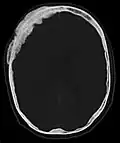

- Aufnahmen pathologischer Frakturen

-

Pathologische Fraktur des Oberarmknochens bei einer Metastase eines Nierenzellkarzinoms -

Pathologische Fraktur des linken Oberarms bei Knochenmetastase einer Patientin mit Brustkrebs -

Ganzkörperknochenszintigramm mit 99mTc-HDP der Patientin mit der Oberarmfraktur aufgrund einer Brustkrebsmetastase